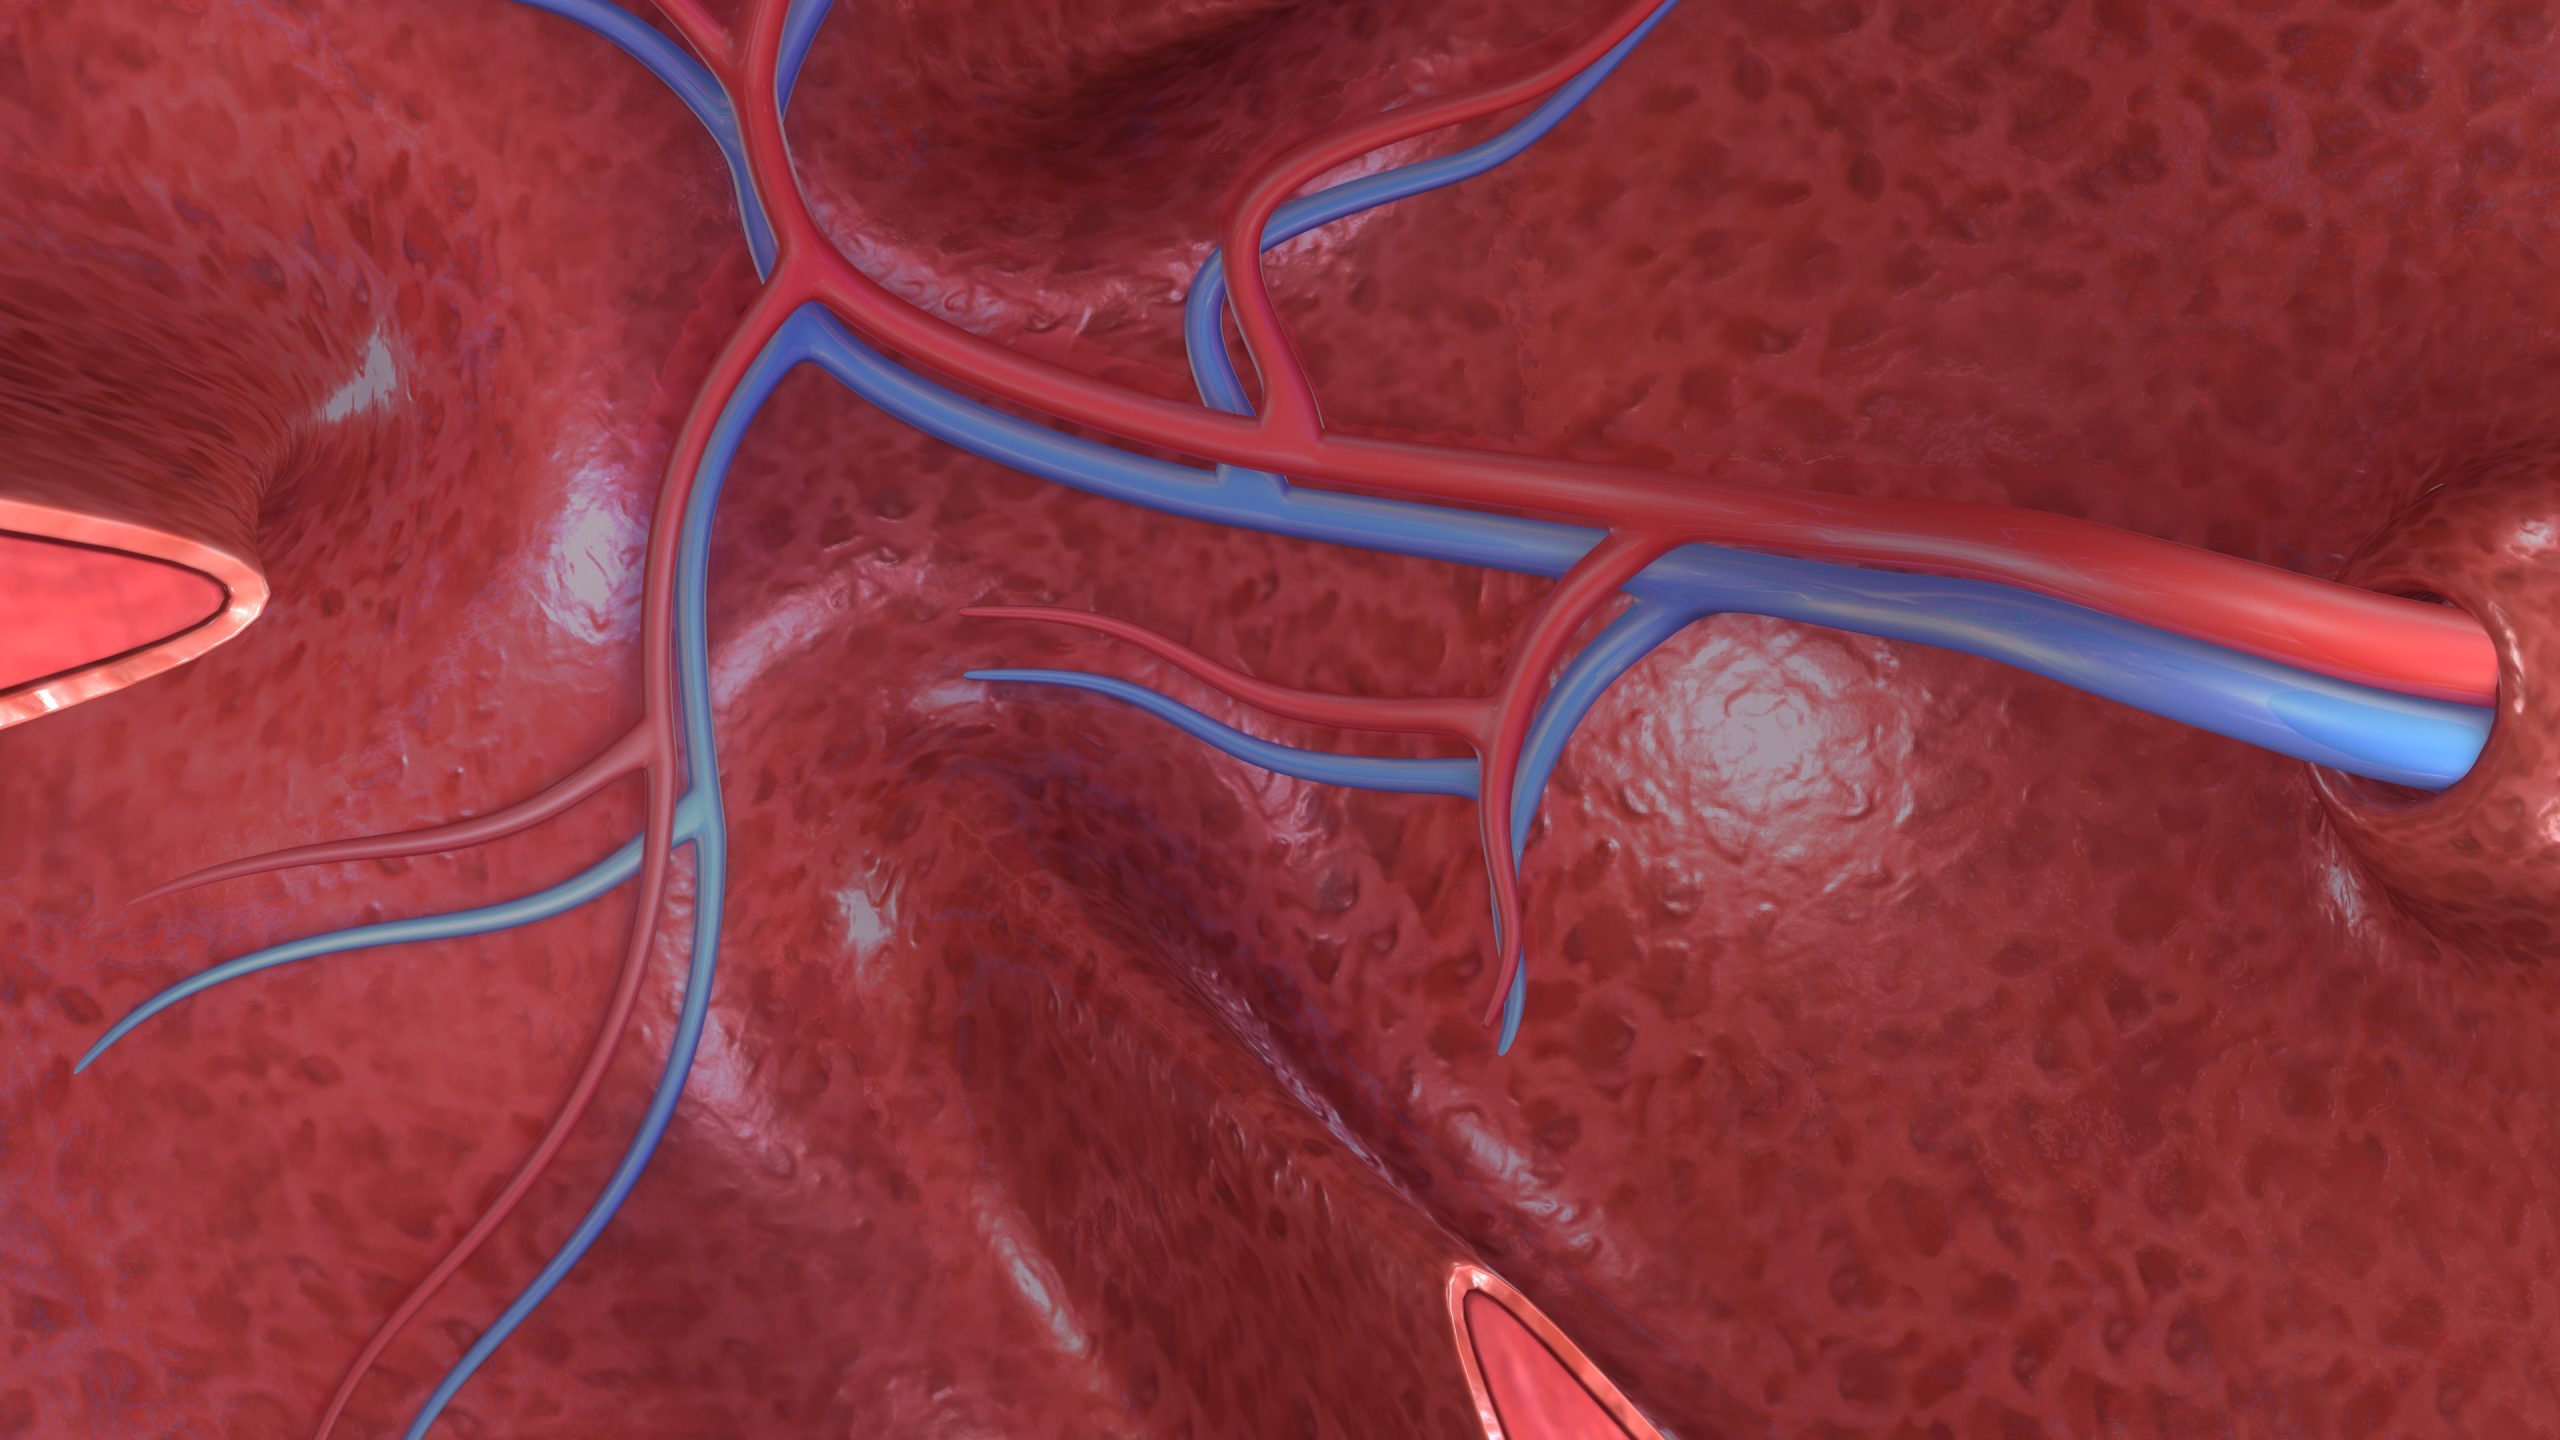

Jakarta, incahospital.co.id – Setiap kali jantung berdetak, darah terpompakan ke seluruh tubuh lewat arteri. Tapi, pernahkah kamu bertanya, bagaimana darah bisa “pulang” kembali ke jantung? Jawabannya: melalui pembuluh darah vena.

Kalau arteri adalah jalan tol menuju seluruh tubuh, vena adalah jalur balik yang membawa darah penuh karbon dioksida dan limbah metabolik kembali ke jantung. Tapi jangan salah, meskipun “jalur balik”, peran vena justru krusial dalam menjaga keseimbangan sirkulasi dan kesehatan organ tubuh.

Secara struktur, pembuluh vena memiliki dinding yang lebih tipis dan kurang elastis dibanding arteri, karena tekanan di dalamnya lebih rendah. Namun yang membuat vena menarik adalah adanya katup satu arah—semacam pintu kecil—yang mencegah darah mengalir mundur. Ini sangat penting, terutama di tungkai dan kaki, di mana darah harus melawan gravitasi untuk bisa naik ke jantung.

Dan satu lagi yang sering disebut: vena cava, yaitu dua pembuluh vena terbesar (superior dan inferior) yang langsung mengalirkan darah ke atrium kanan jantung.

Ketika kita bicara tentang sirkulasi darah, banyak orang terlalu fokus pada jantung dan arteri. Tapi faktanya, tanpa vena, siklus hidup darah akan terputus. Itulah kenapa gangguan pada vena bisa berujung ke masalah serius seperti pembengkakan, nyeri kronis, hingga bekuan darah yang mengancam jiwa.